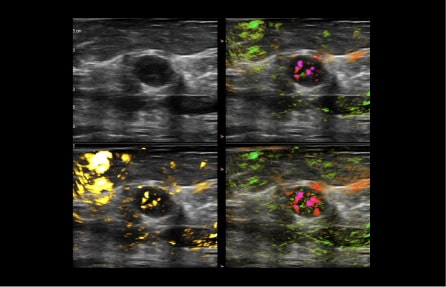

Signals from the sensors are analyzed and co-registered into images that present a real-time blood map of the lesion in easy to distinguish colors. OA image contrast is related to both blood volume and oxygenation status.

In general, malignant masses are more vascular and deplete oxygen from the blood at a higher rate than do benign masses. The two wavelengths of laser light used in the Imagio® system facilitate imaging by showing the relative differences between oxygenated and deoxygenated blood.

With the Imagio® Breast Imaging System, clinicians have been able to identify and classify tumors as small as 3 millimeters, as well as visualize vascular structures smaller than one millimeter.